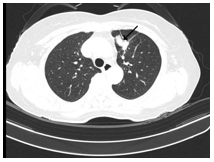

-         Cắt lớp vi tính ngực (Bệnh viện Bạch Mai): Phổi trái: Phân thùy S3 có khối tỷ trọng tổ chức kích thước 24x15mm, ngấm thuốc sau tiêm bờ không đều xâm lấn vào màng phổi trung thất, động mạch, tĩnh mạch phổi trái gây huyết khối bán phần.Xẹp thụ động thùy dưới. Màng phổi trái: có nốt ngấm thuốc đường kính 8mm. Dịch khoang màng phổi trái dày 60mm gây xẹp thụ động thùy dưới. Hạch trung thất nhóm V, nhóm II, IV bên phải và carina lớn nhất kích thước 23x12mm. Hình ảnh tổn thương tiêu xương đòn trái.

Hình 1: Hình ảnh cắt lớp vi tính ngực lúc mới nhập viện: Khối tổn thương thùy trên phổi trái, tỷ trọng tổ chức, bờ không đều, ngấm thuốc không đồng nhất, xâm lấn màng phổi trung thất (mũi tên màu đỏ). Tràn dịch màng phổi trái lượng nhiều gây xẹp phổi thụ động thùy dưới (mũi tên màu vàng).